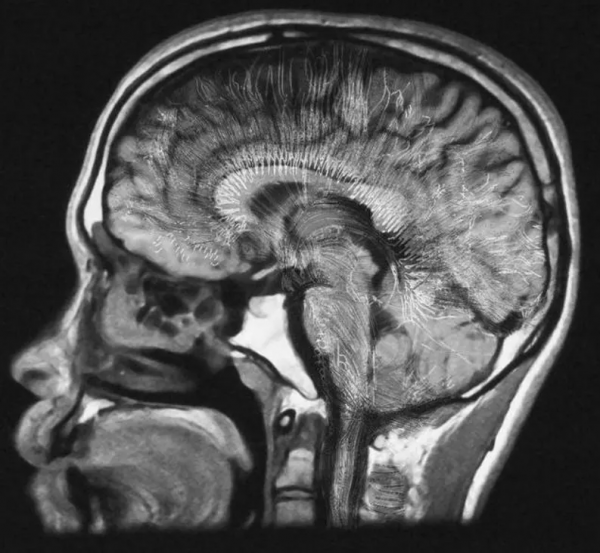

至於大腦如何維持我們的思想和意識,我們仍然知之甚少。不過隨著成像技術的進步,在一定程度上揭示了大腦不同區域的神經元如何在不同的刺激下激發放電,就像聖誕樹上的燈一樣。

上面說的是理解神經元執行方式的簡單部分。而困難的部分,則是瞭解活躍的神經元如何共同創造出「我們是誰」的感覺的。也就是說,生物電活動和血液流動,是如何轉化為自我意識的。

有人提出,要了解大腦,必須沿著自下而上道路:從單個神經元到突觸連結,再到在它們之間流動的神經遞質,再到神經元簇和大腦回路。

畢竟,如果我們採用自下而上的方法,大腦是由神經元組成的,和任何其他細胞一樣,神經元需要蛋白質和大量生物分子才能發揮作用。由於量子效應發生在分子水平,因此量子力學有可能在意識的產生中起到了一些關鍵作用。